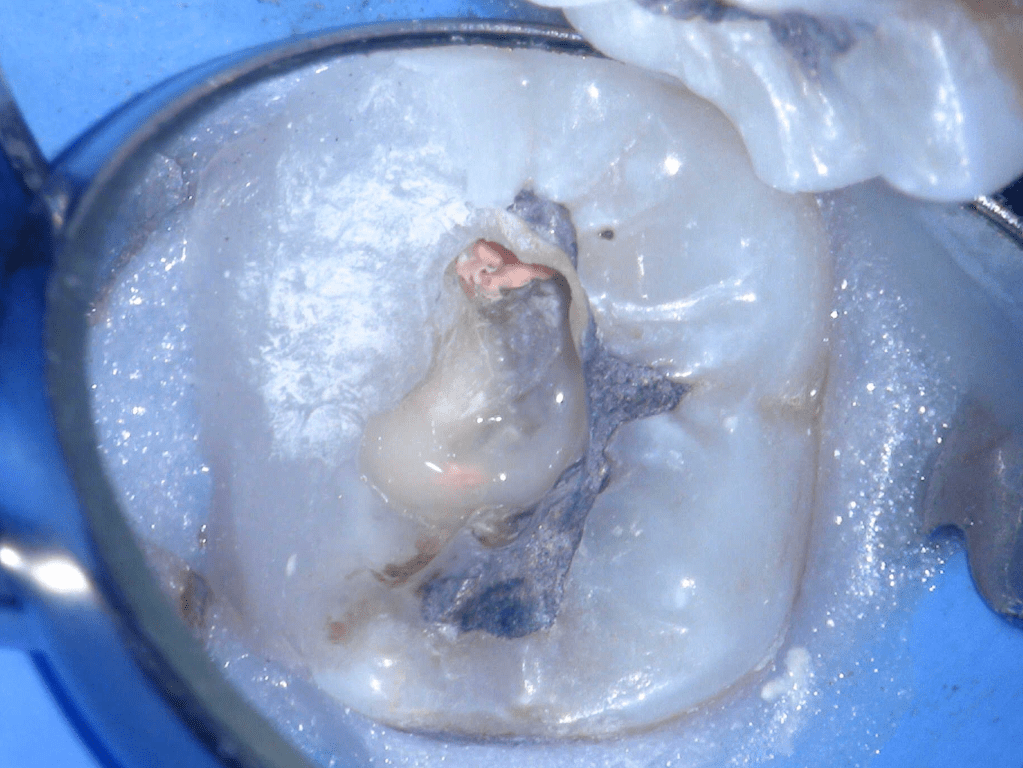

Fisura, remoción amalgama para explorar